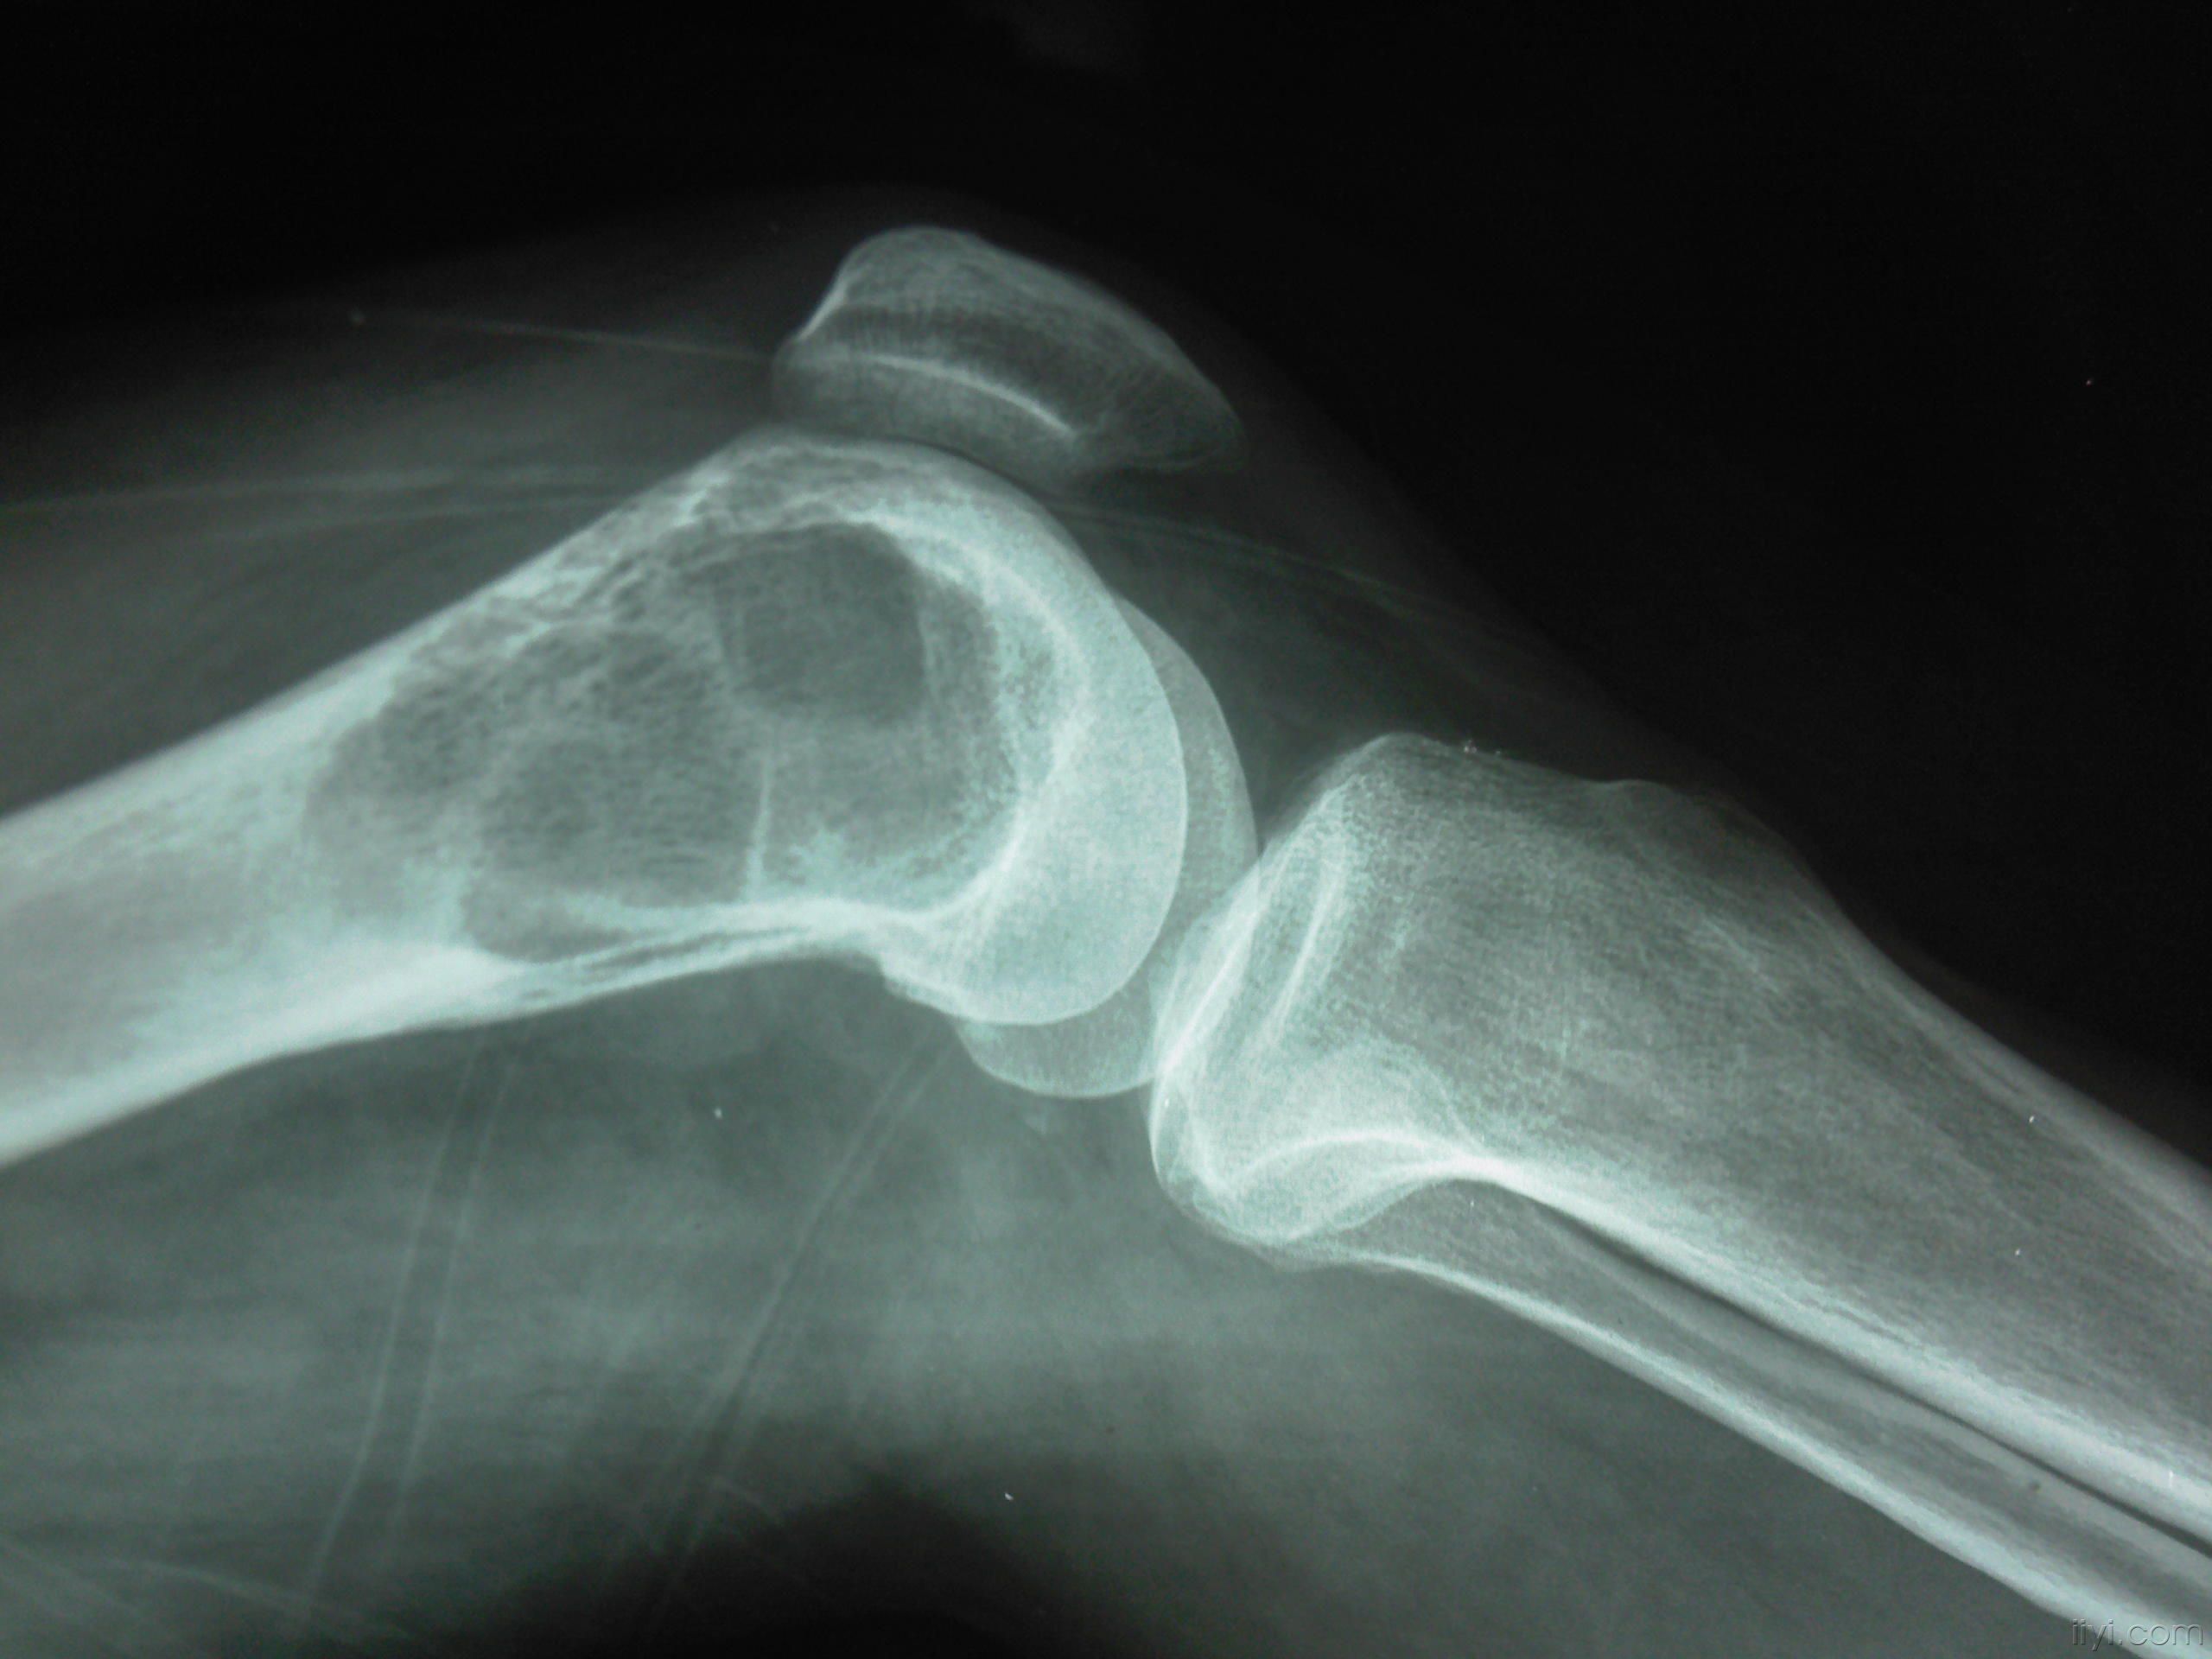

骨巨细胞瘤由软而脆且易出血的肉芽样组织所构成,无纤维包囊。由于瘤组织易出血和坏死,故可出现多种多样的病变。因血红蛋白的变化,可使肿,自呈红棕色或绿色。血肿的纤维化可使肿瘤呈灰白色。瘤组织坏死,可使肿瘤呈黄色或形成假囊肿,囊内可能含有胶状或棕色液体,骨质因肿瘤扩张压迫而萎缩,当骨膜下的皮质骨萎缩消失后,骨膜即产生新生骨,在肿瘤进展中新骨消失和再生继续反复,以致在x线照片上皮质骨似乎有被肿瘤由内向外扩张而变薄的错觉。

(一)多发于四肢长骨,其中尤以股骨远端,胫骨近端,桡骨远端及股骨近端为多见。

(三)主要症状是局部疼痛及压痛。肿瘤发展,局部肿胀变形,温度略有增高。因骨质膨胀扩张,触之有捏乒乓球样感觉。

(五)大量骨质破坏、容易形成病理性骨折。